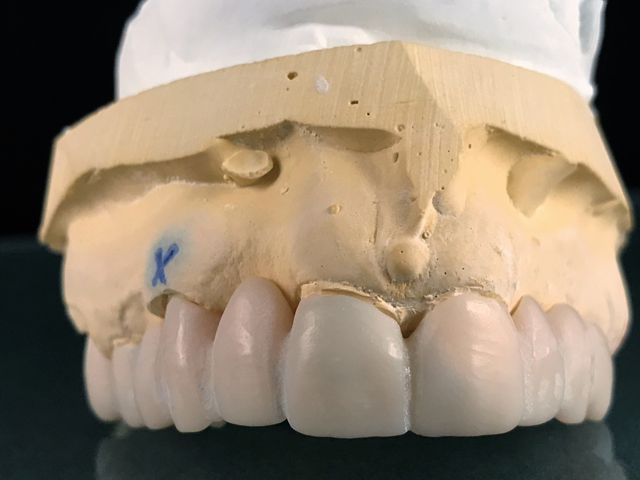

Here is the finished case before sending it back to the dentist (Figs. 23-25) and here is the final seated case (Figs. 26-28).

Fig. 23                                                                            Fig. 24

Fig. 25                                                                   Fig. 26